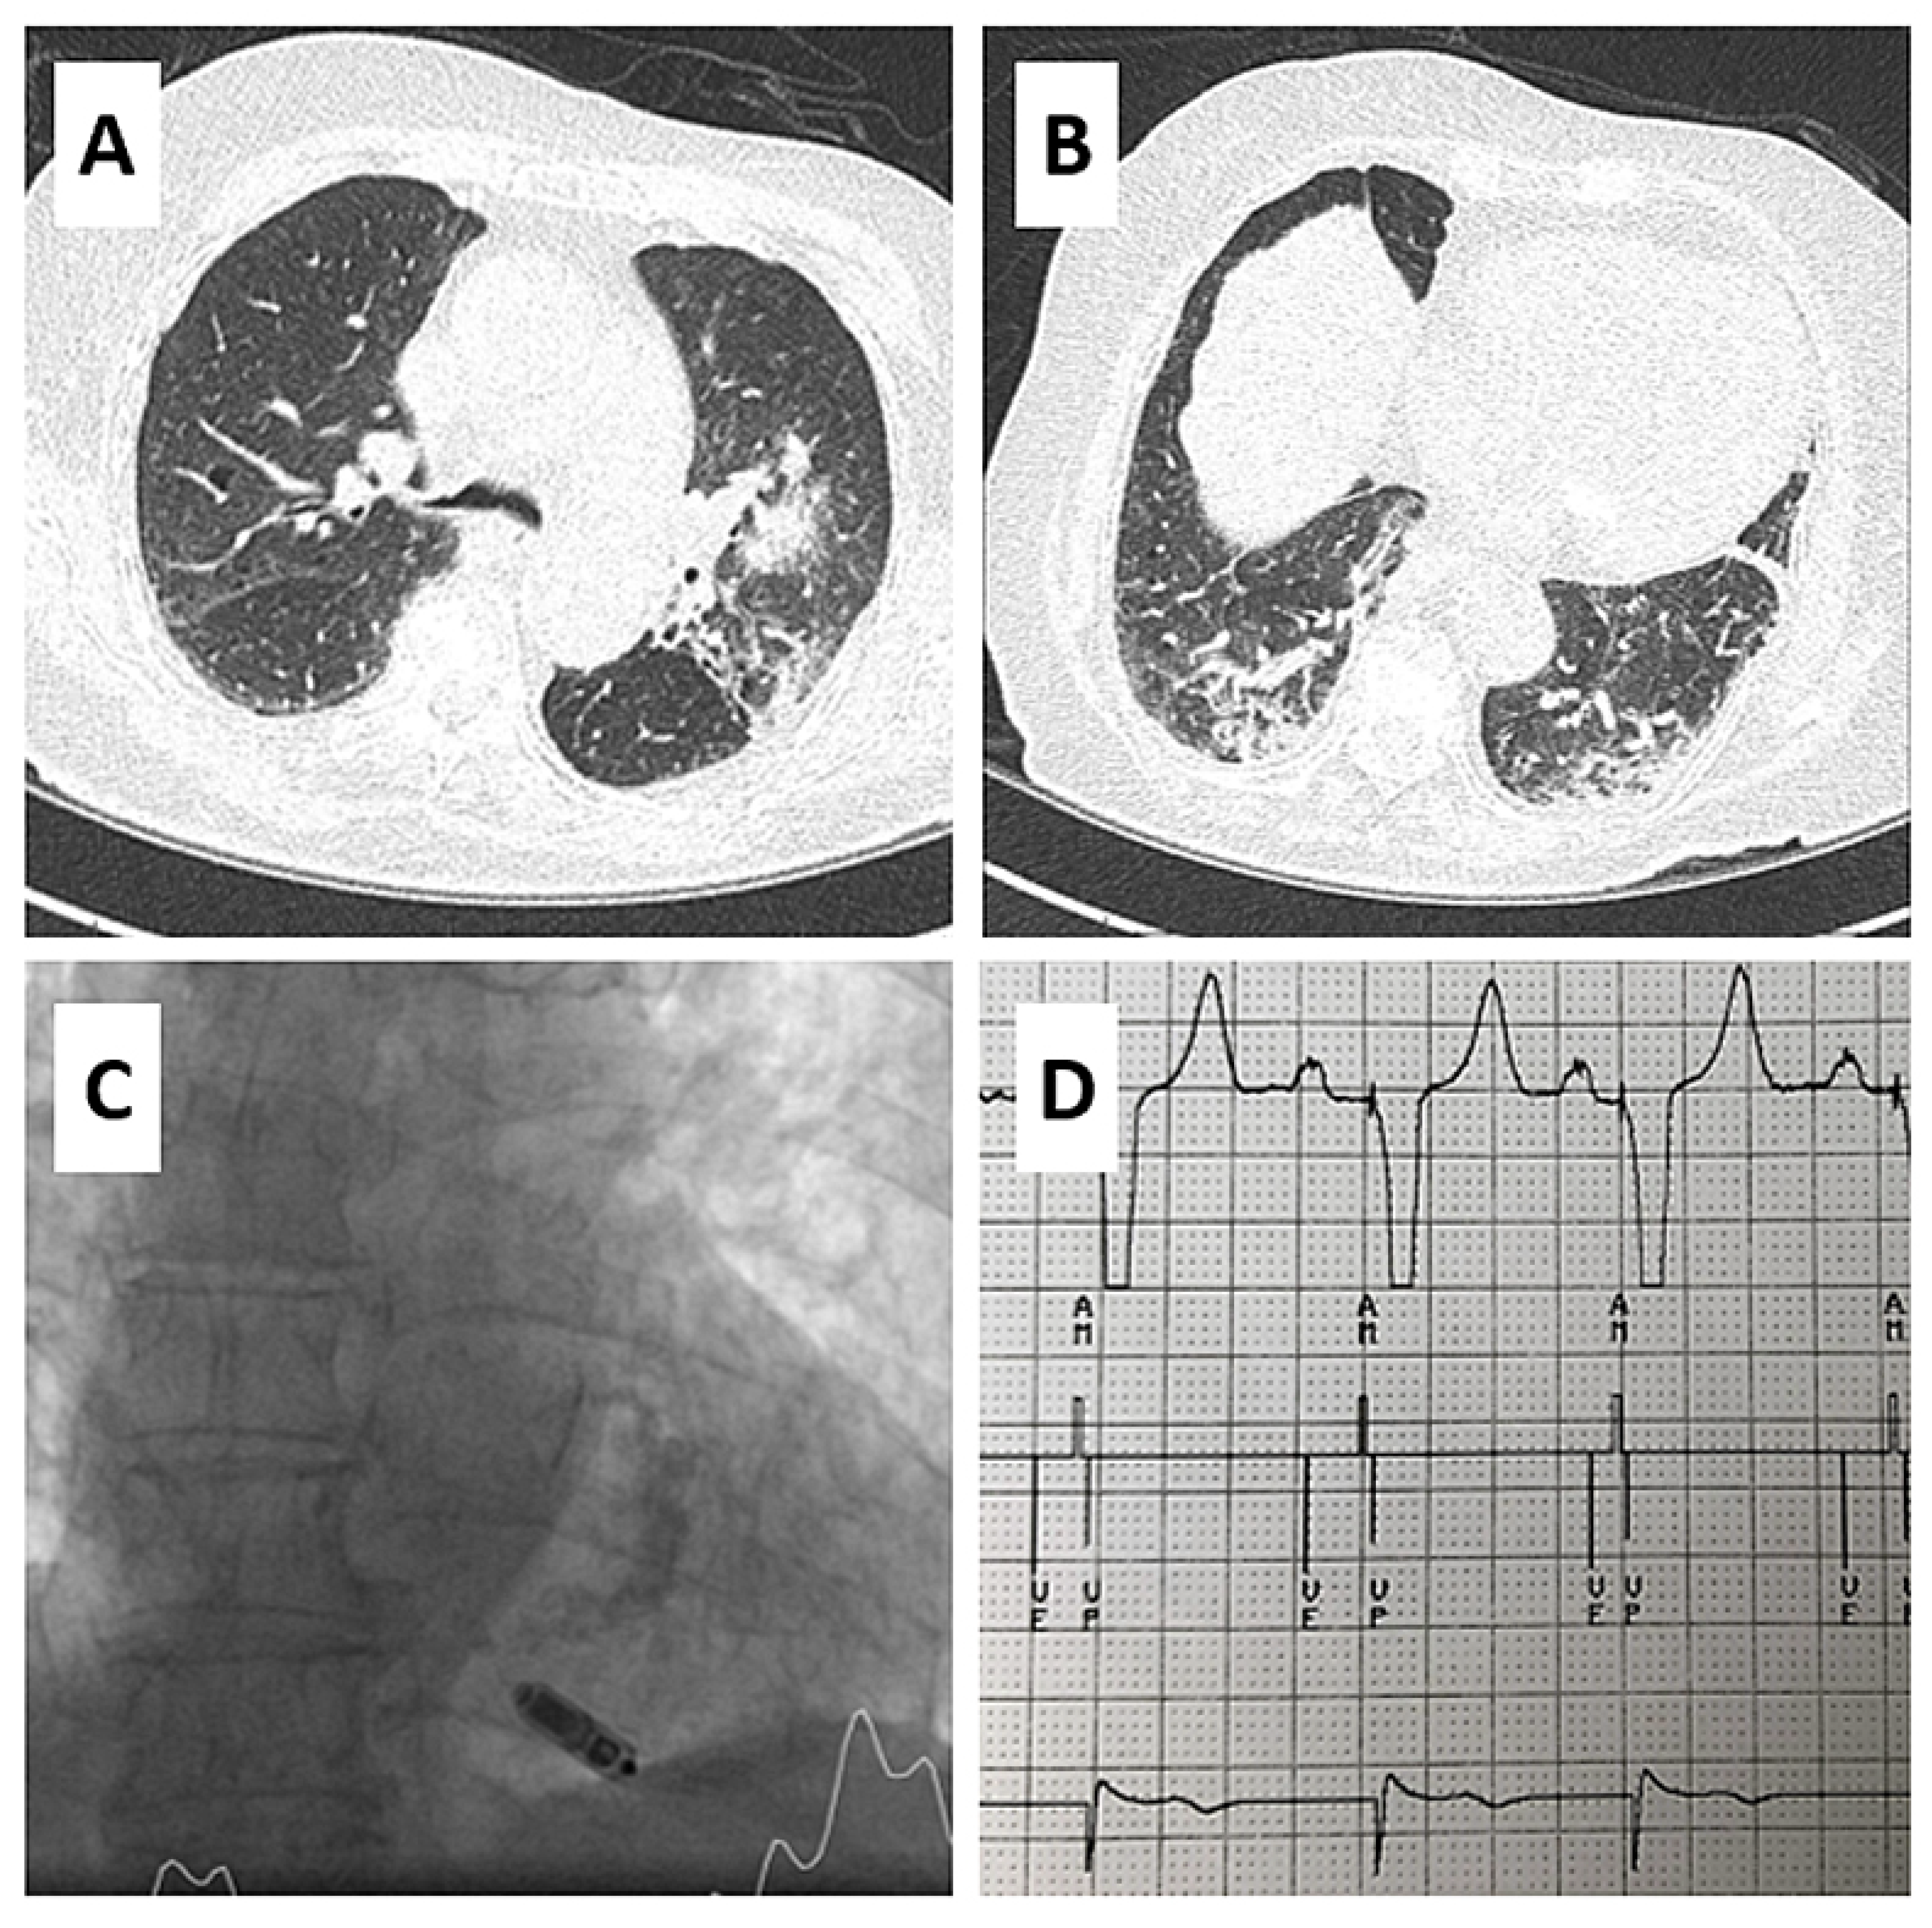

AV Synchronous Pacing with a Single-Chamber Leadless Pacemaker in a Patient with COVID-19 and Complete AV Block

Case report